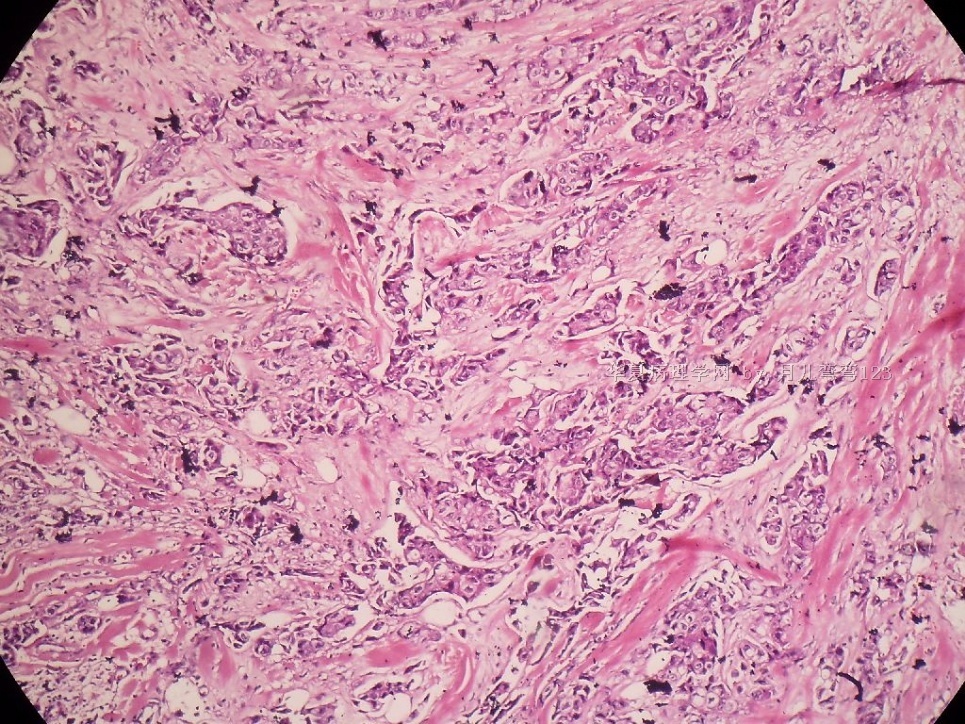

姓    名: ××× 性别:  女 年龄:  45

标本名称:  左侧近乳晕处肿物

简要病史:  患者描述有疼痛

肉眼检查:  肿物一个2.5*2*1厘米,切面灰白质地硬。

• 浸润性导管癌?图1

图1

上皮样细胞,大部分粘附成团成巢,明显浸润。大部分细胞大,核级别高,少数图中见松散的小细胞。未见原位癌。

大细胞考虑浸润性导管癌(3级),小细胞要排除小叶癌。如果有条件请做免疫组化。

Most likely it is INVASIVE DUCTAL CARCINOMA.

DO ER/PR/HER2 STAINS

应该是浸润性导管癌,标本可能有部分自溶现象。